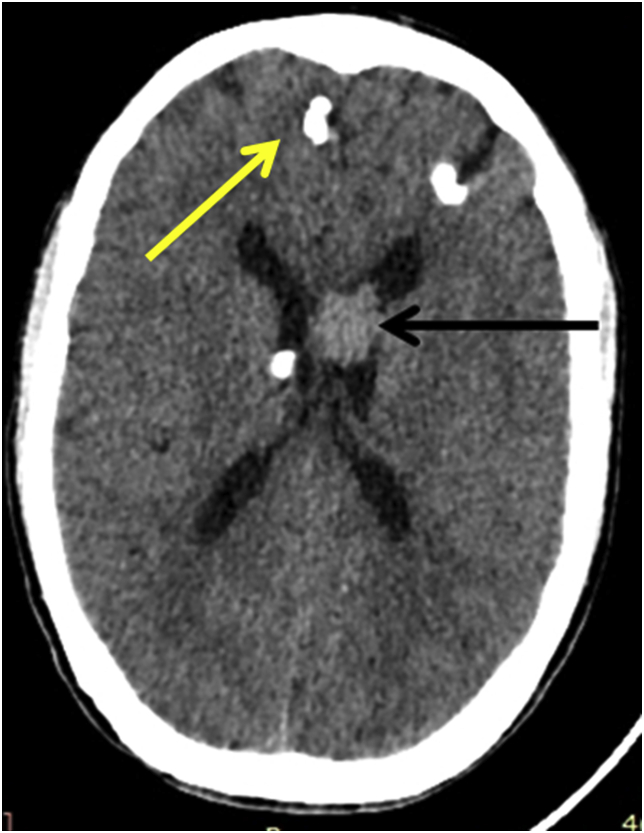

Laboratory examination revealed normal hemogram, liver function, renal function, and serum electrolyte. Non-contrast computed tomography (NCCT) scan of the brain showed multiple calcified subcortical nodules (yellow arrowhead, Fig. 2) and left lateral ventricle lesion (black arrowhead, Fig. 2). For a better characterization of the lesion, the MRI brain was done, which revealed a heterogenous contrast-enhancing lesion in the left lateral ventricle. The lesion was hypointense on T1, T2 sequences, and hyperintense on FLAIR sequences, suggestive of giant cell astrocytoma (Fig. 3).

Fig. 2.

Noncontract Computed tomography (NCCT) scan of the brain showed multiple calcified subcortical nodules (yellow arrowhead) and left lateral ventricle lesion (Black arrowhead).